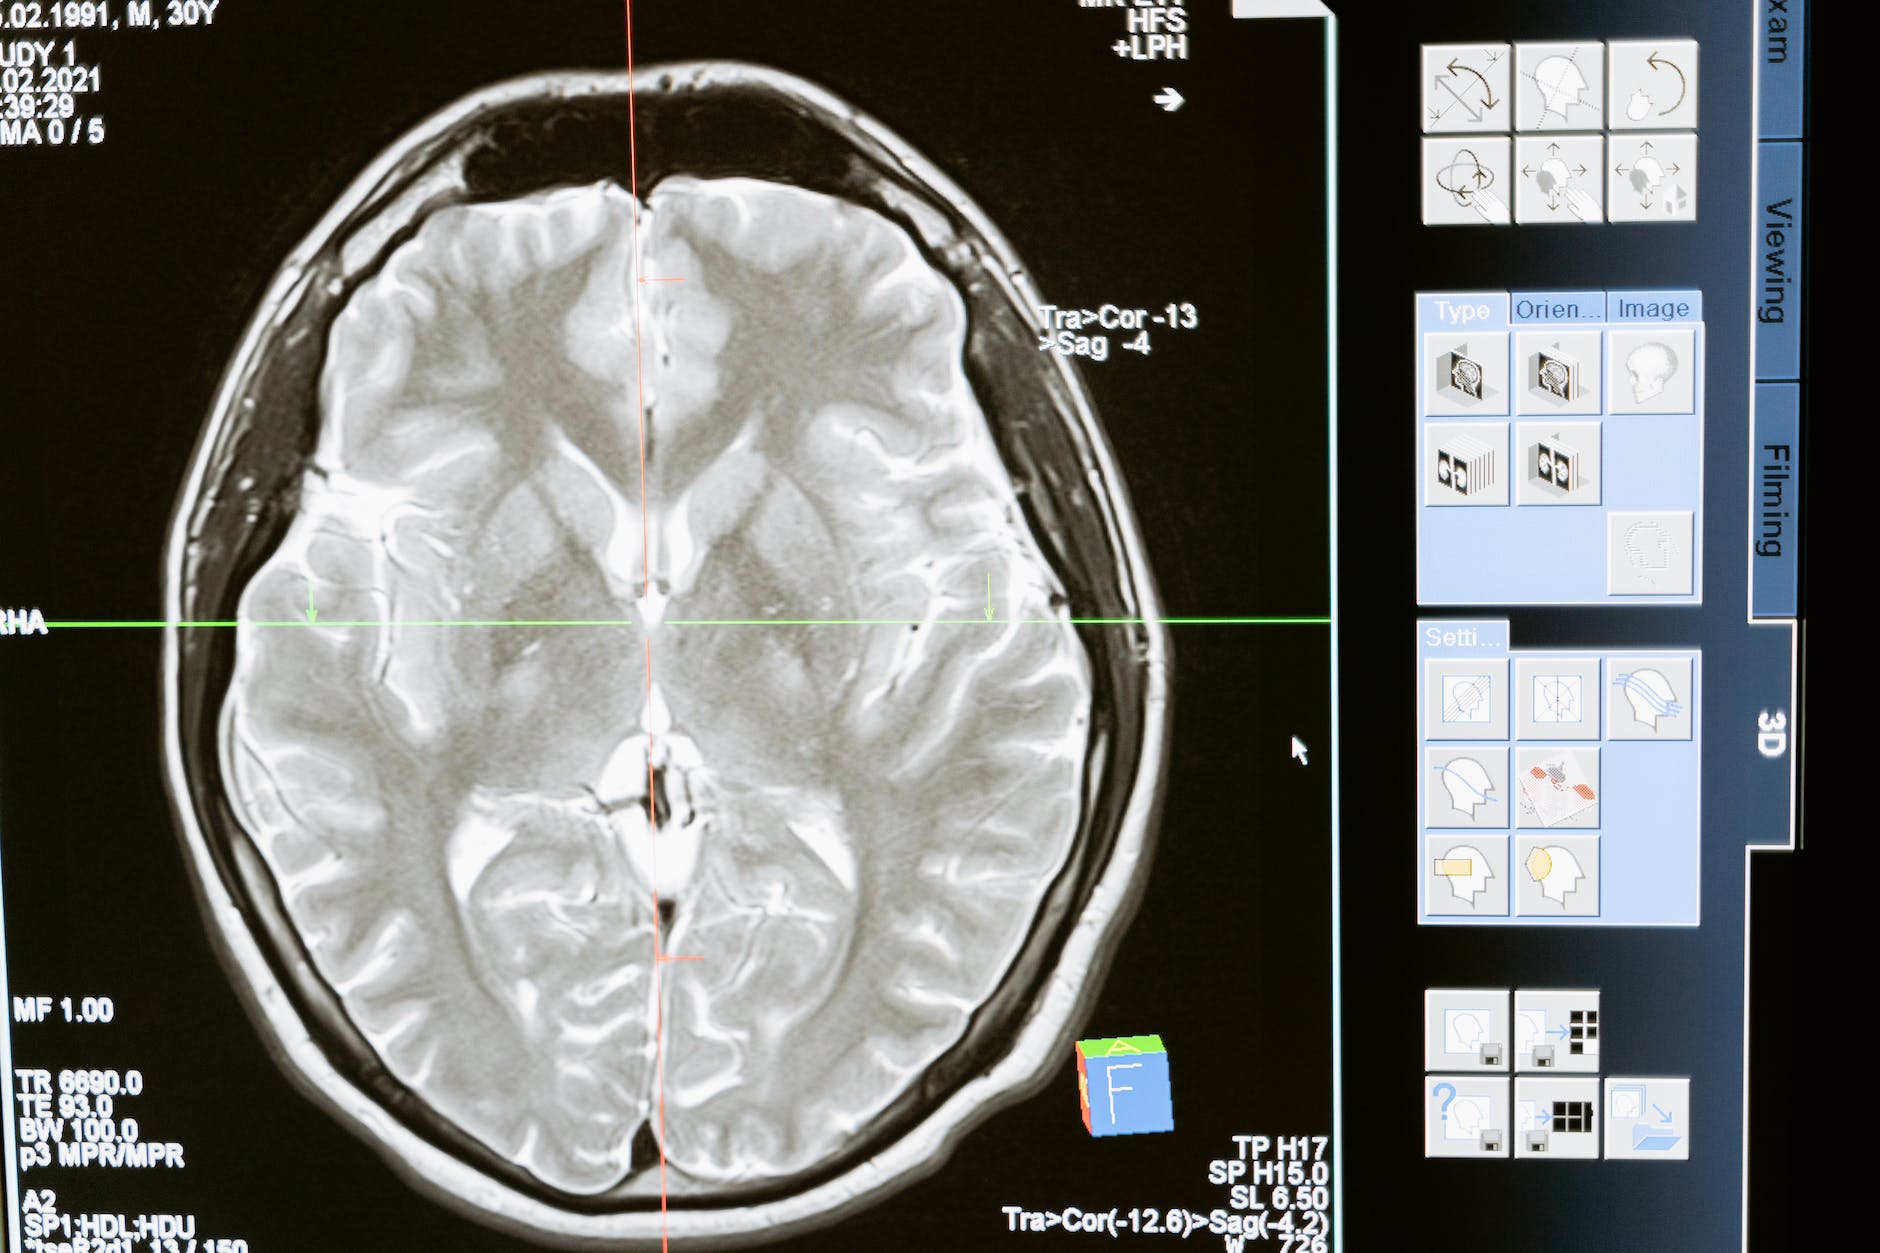

Activation of the Medial Prefrontal Cortex

Have you ever had a “flow” moment in volleyball, where everything just clicks? That’s partly thanks to the medial prefrontal cortex (mPFC). This brain region is like a conductor, orchestrating self-reflection, decision-making, and even empathy. Gratitude lights up the mPFC, enhancing your ability to make calculated choices during intense moments on the court. It’s like having a secret weapon that lets you read the game and anticipate moves like a pro.

“Gratitude lights up the mPFC (medial prefrontal cortex), enhancing your ability to make calculated choices during intense moments on the court.”